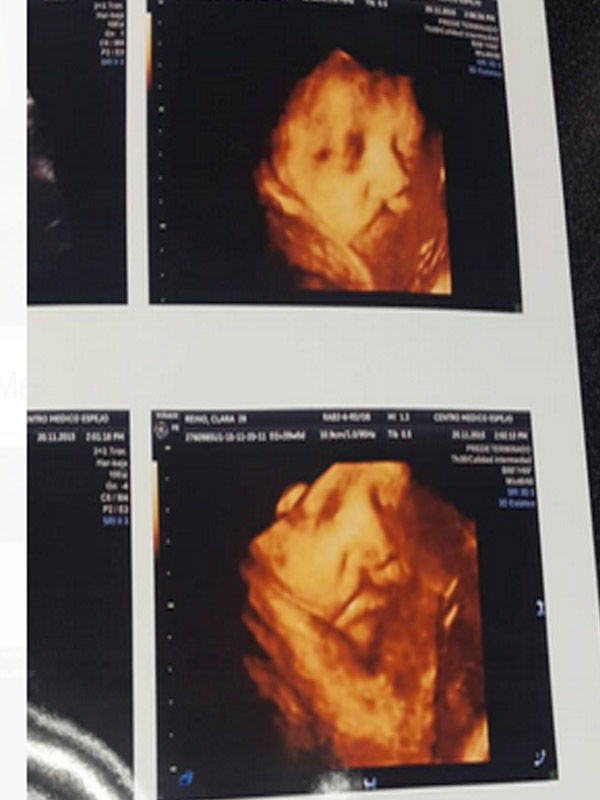

Entre la 11va y 14 semanas de gestación, (preferentemente semana 12), puedes realizarte la prueba combinada (ecografía + prueba de sangre), se sugiere realizar screening para Detectar las posibles malformaciones y marcadores ecográficos de cromosomopatías, se valora translucencia nucal, ductus venosos, hueso nasal, entre otros que nos permite identificar el riesgo para el diagnóstico de Síndrome de Down (el más común), síndrome DE Patau, Sd. Edwars, etc.

Además, nos permite Valoración anatómica precoz, marcadores ecográficos tempranos para preeclampsia (arterias uterinas), parto prematuro.

Segundo Trimestre O Ecografía Morfológica: Se la realiza en la semana 20-22 de gestación (preferentemente semana 21). Tiene como objetivo la valoración ecográfica la anatomía de tu bebé, realizando un examen detallado de toda su morfología, para descartar malformaciones estructurales como ventriculomegalia (hidrocefalia), labio leporino, malformaciones cardiacas, espina bífida, malformaciones pulmonares, intestinales, genitourinarias, de la pared abdominal y esqueléticas, además valoración de la placenta, inserción del cordón y líquido amniótico, valoración del crecimiento fetal. Confirmar edad gestacional de acuerdo a biometría fetal y mediante estos parámetros evaluar el crecimiento fetal.